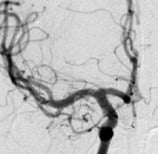

Angiografia projeção frontal mostrando o volumoso aneurisma cerebral.

Angiografia digital projeção perfil mostrando 2 aneurismas cerebrais.

Reconstrução 3D da angiotomografia projeção frontal mostrando o volumoso aneurisma cerebral.

Reconstrução 3D da angiotomografia projeção perfil mostrando o aneurisma cerebral.

Reconstrução 3D da angiotomografia após a cirurgia no cérebro e clipagem do aneurisma cerebral.